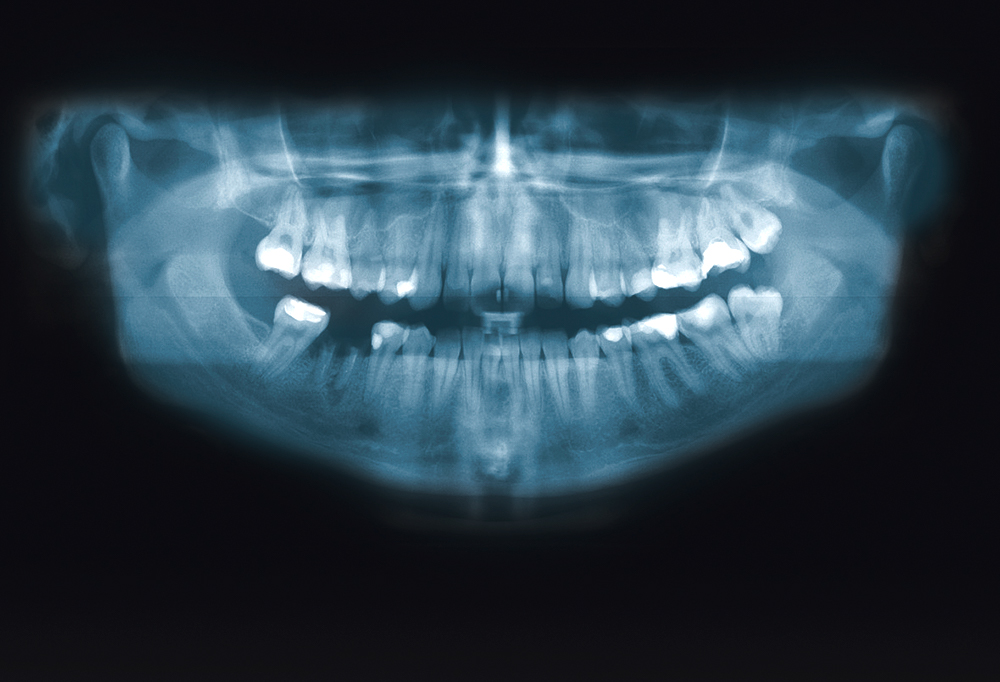

Noin joka seitsemäs varusmiesten tapaturmista on hammasvamma.

Varusmiehet laiminlyövät hammashygieniaa – hammaslääkärit huolestuneita

Nuorten hampaat ovat heikommassa kunnossa kuin pari vuosikymmentä sitten. Varusmiesten nuuskan käyttö ja napostelu ovat hammaslääkärien painajainen.

Varusmiehistä joka toisella on hammashoidon tarvetta jo palveluksen alkaessa. Paikkaushoidon tarpeessa olevien hampaiden määrä on laskenut muutaman vuosikymmenen aikana, mutta kehitys on hidastunut huomattavasti. Vielä vuonna 1979 varusmiehillä oli keskimäärin neljä paikkaushoidon tarpeessa olevaa hammasta. Vuonna 2015 luku oli enää noin 1,4 hammasta, mutta puolustusvoimien ylihammaslääkäri, lääkintäkomentaja Pertti Patinen kertoo, ettei uusimmissa tutkimuksissa ole huomioitu yhtä tunnetuinta haittaa – viisaudenhampaita.

Palveluksessa tapahtuvista tapaturmista noin 14 prosenttia on hammasvammoja. Niiden yleisin syy on liukastuminen tai rynnäkkökiväärin osuminen etuhampaaseen – johtaen yleensä lohkeamiseen. Valtaosa noin kahdestasadasta varusmiehen hammasvauriosta vuosittain on lieviä, mutta jälkivaikutuksia voidaan todeta vielä vuosienkin jälkeen.